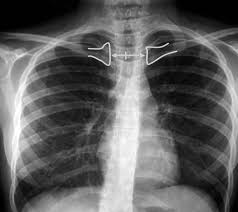

¿Que músculos se insertan en la clavícula?

La clavícula es un hueso largo y delgado situado en la parte superior y frontal del tórax humano, extendiéndose desde el manubrio esternal hasta el acromion de la escápula. Su…